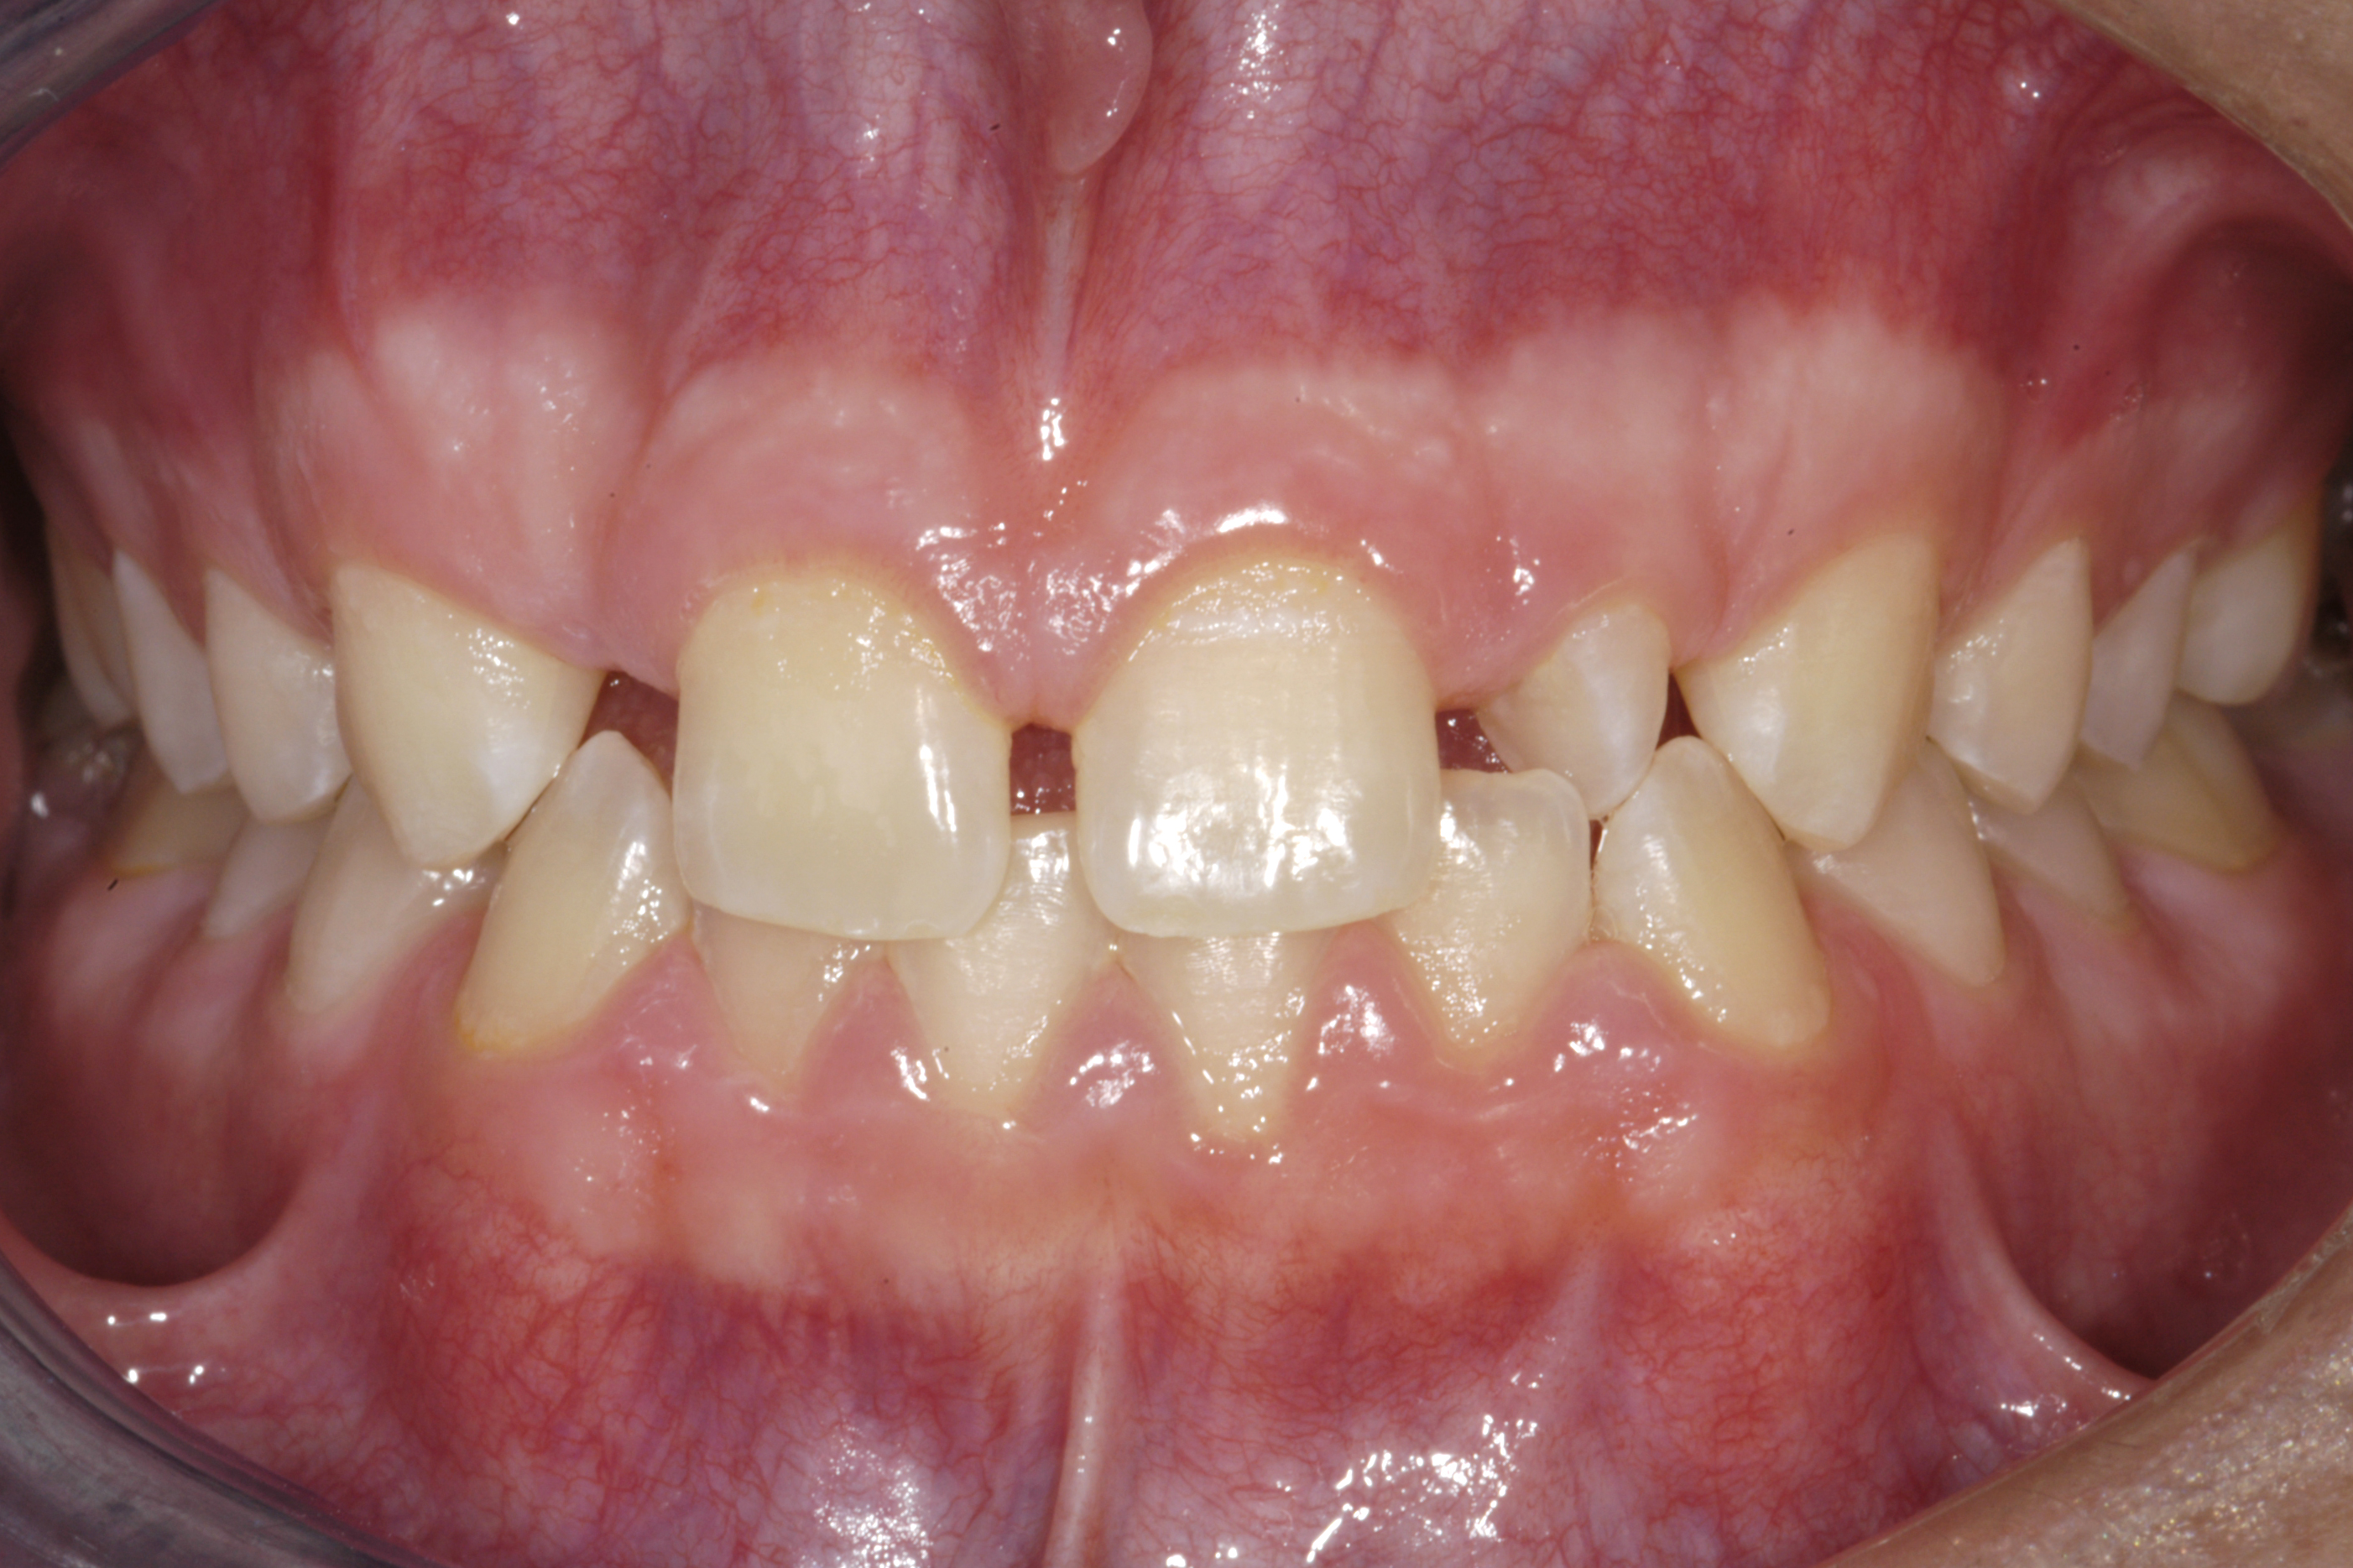

(1.) Initial presentation. Note midline shift to right, missing right lateral incisor, and diminutive left lateral incisor in crossbite.

Figure 1

A 14-year-old patient presented to the office with his mother (Figure 1). His chief complaint involved the large spaces between the teeth created by his missing right maxillary lateral incisor and his small left maxillary lateral incisor. He desired to replace the missing tooth with an implant and create a beautiful smile. Upon examination, he was found to have a class I canine and molar relationship, but because he had a tooth size/arch size discrepancy and space distal to the right central incisor, the remaining incisors had drifted to the right. The left maxillary lateral incisor was peg-shaped and in a cross bite position. Studies have shown a clear association between congenitally missing teeth and reduced tooth size.59-62 Because he was only 14-years-old at the time and could not have implants placed until the cessation of growth (somewhere in the vicinity of 22 years old), he was sent to the orthodontist for alignment of the teeth.16,17 After 2 years of orthodontics, the appliances were removed, and his tooth coloration was improved using carbamide peroxide bleaching (Figure 2). Because some form of provisional needed to be placed until he was finished growing, a double-wing metal resin-bonded bridge was chosen. As discussed earlier, this is the ideal transitional prosthesis for patients that have congenitally missing maxillary lateral incisors. The benefits of this type of prosthesis include its ability to be removed and rebonded during the surgical phase of treatment and its ability to retain the roots in their proper position after orthodontic treatment.16 The final plan for the patient was to increase the width of the central and the maxillary left lateral incisor, utilizing porcelain laminate veneers to achieve the appropriate width/length ratio of 80%. A wax-up was created to idealize tooth size, a putty matrix was made from the wax-up to facilitate bonding of the incisors, and a non-precious, double-wing metal resin-bonded bridge was fabricated for lateral incisor replacement. Once the teeth were bonded to ideal size, the “Maryland Bridge” was fabricated from a polyvinyl arch impression with the newly bonded teeth (Figure 3). The metal frame was cast from a non-precious alloy to allow for fabrication of a very thin frame and to create a better surface for bonding. After sandblasting the internal aspect of the frame with CoJet™ silica (3M ESPE), accomplishing salinization, and executing cementation with a dual-cure resin cement, a fairly good adhesion to the frame was anticipated.29 The enamel surface was etched with phosphoric acid for 30 seconds, the primer (Single Bond Plus, 3M ESPE) was applied to both the internal surface of the sandblasted framework and the etched enamel, and the bridge was cemented with RelyX™ ARC (3M Espe) dual-cured resin cement (Figure 4 and Figure 5).